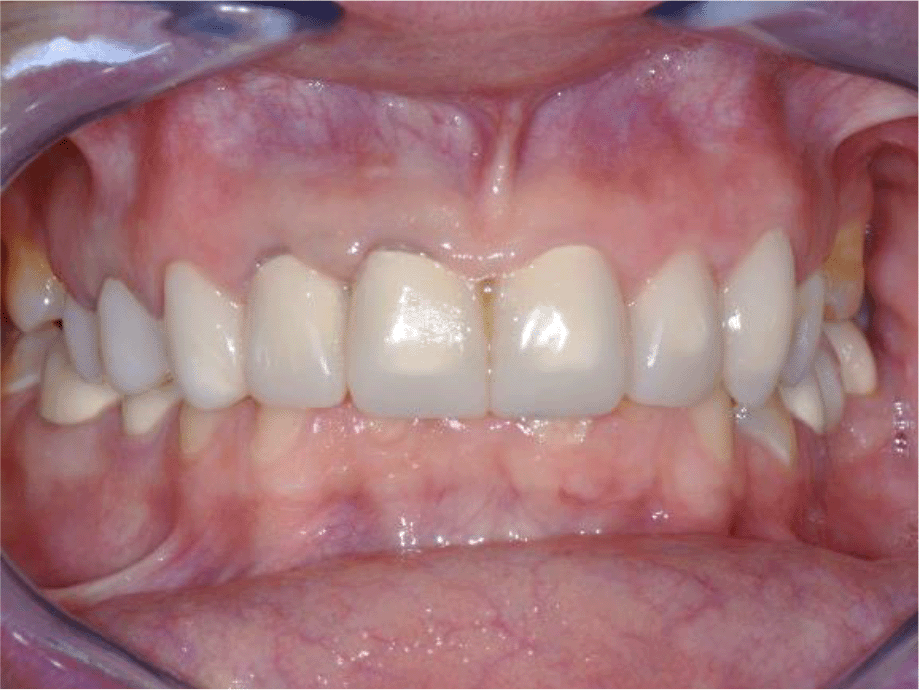

The patient reported a lack of symptoms of TMJ after 3 months, establishing the therapeutic effect of the splint. We then proceeded to the final prosthesis. All constructions were made of ceramics based on zirconium dioxide, with added yttrium and hafnium oxides. The distal defects of the lower jaw were solved with bridge constructions, and single crowns were placed on the frontal teeth (Figures 19 and 20).

26dd931c-41d3-478d-bec1-8cb211d0a4b8_figure19.gif

Figure 19. Zirconia prosthesis on the model.

26dd931c-41d3-478d-bec1-8cb211d0a4b8_figure20.gif

Figure 20. Zirconia prosthesis in the patient’s mouth (try-in procedure).

All of the final constructions were made from Ceramill Zolid FX MultiLayer B2 and Glase (AmannGirrbach). For the upper jaw, single zirconia crowns of the canines and block crowns of 11, 12 and 21, 22, respectively, were made, for the distal defects - bridge restorations of zirconia ceramics. The distal structures of both jaws were cemented first to ensure stable occlusion. Then the crowns were fixed almost at the same time in the frontal section (Figures 21 and 22).

26dd931c-41d3-478d-bec1-8cb211d0a4b8_figure21.gif

Figure 21. Lower zirconia crowns, upper PMMA during the try-in procedure.

26dd931c-41d3-478d-bec1-8cb211d0a4b8_figure22.gif

Figure 22. Upper and lower zirconia crowns.

Follow up and outcomes

Follow-up was performed at each new step throughout treatment. No adaptation period was observed after the final prosthesis. The patient was scheduled for periodic monitoring at 3 months. No clinical symptoms of the TMJ were found, the patient also did not report.